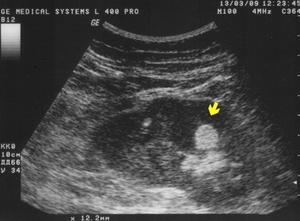

Еще одним методом диагностики является ультразвуковое исследование (УЗИ). С его помощью можно выявить любые новообразования в внутренних органах.